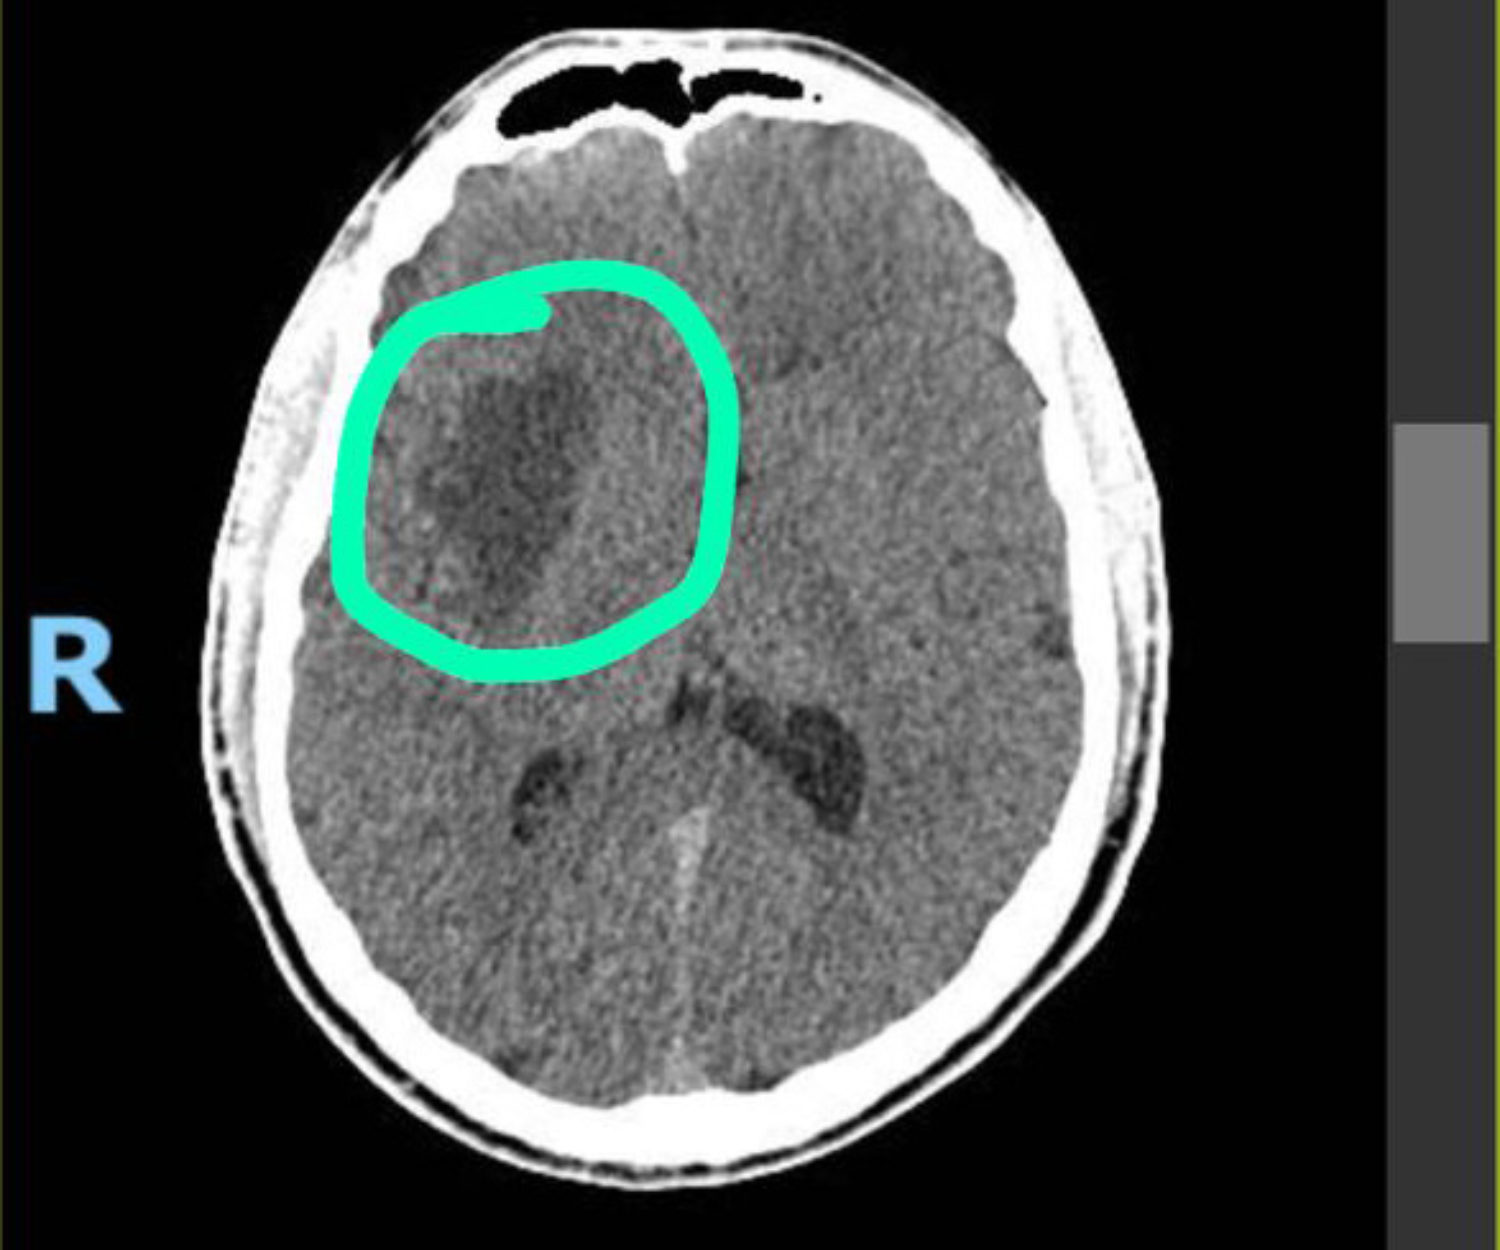

Em março de 2021, tive uma convulsão logo antes de dormir e, dias depois, fui diagnosticado com um astrocitoma de baixo grau de tamanho similar à uma bola de golfe. Fui operado em maio e faço ressonâncias de controle regularmente desde então. Nessa série de textos, registrei a descoberta, o baque, a força que recebi de amigos e família, as cirurgias e como é legal e importante ter uma rede de apoio.